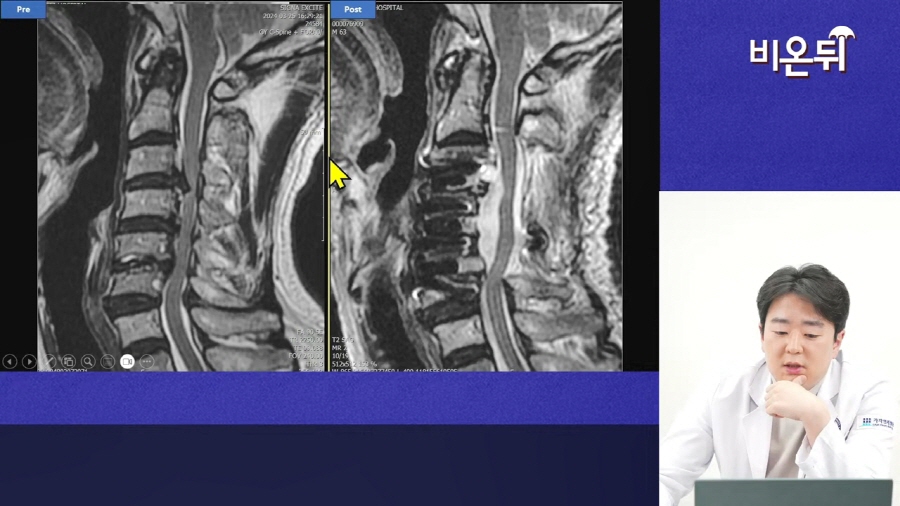

이어서 3가지 실제 환자 사례를 통해 더 이해하기 쉽게 설명해주셨는데요.

후종인대골화증으로 한 쪽 팔을 제대로 들지 못하고 절뚝거리면서 보행에도 장애가 있었던 60대 남성분도

후종인대골화증으로 진단을 받았고, 수술을 받은 후 다시 정상적인 보행을 되찾을 수 있었습니다.